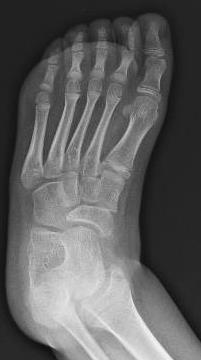

´Following orthopedic specialist visit, surgical correction of bilateral equinus foot was indicated

Fibrotomy-based Achilles tendon lengthening performed, achieving correction of equinus

deformity and full ankle dorsiflexionª